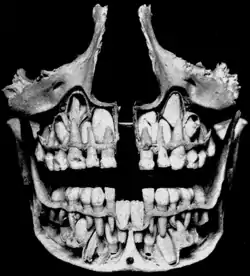

Deciduous teeth

Cross-section of upper and lower jaws with permanent teeth located above and below the deciduous teeth prior to their exfoliation. The deciduous mandibular central incisors have already been exfoliated.